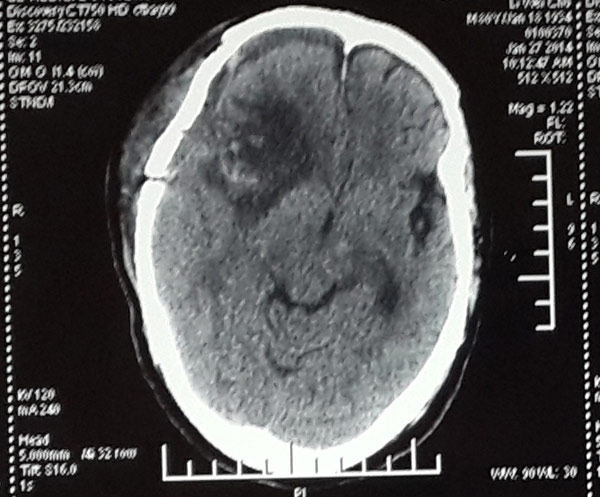

头颅CT显示,李大爷颅内肿瘤已经长至鸭蛋大小,立即手术是挽救老人生命的唯一办法。

通过手术探查,医生发现肿瘤侵占了整个脑颅近一半的空间,“李大爷的右边大脑组织已经受到肿瘤的挤压变形,再不手术李大爷很有可能出现出现生命危险。”神经外科张雅轩医生介绍。

术后脑膜瘤被完整移除